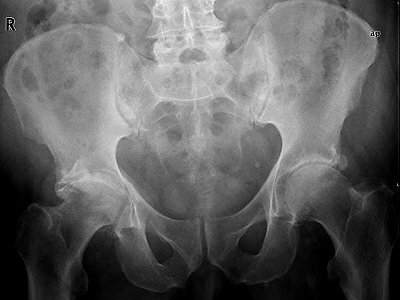

Knochen